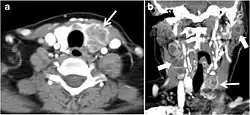

Fig. 4. A 45-year-old male patient presented with anterior mediastinal metastatic PTC lesions and occult primary on imaging. Histopathology examination of the resected thyroid gland revealed micro-foci of PTC; the largest, in the isthmus, measured 4 mm. a transverse greyscale ultrasound of the thyroid demonstrates homogeneous gland with normal echogenicity and size. No focal lesion or micro-calcifications. b Non-enhanced CT scan obtained as part of PET/CT examination shows a heterogeneous, large, relatively dense anterior mediastinal mass (white arrow) with peripheral calcification (arrowheads). Thyroid gland has normal CT appearance with no abnormal FDG uptake (not shown).[1]

-